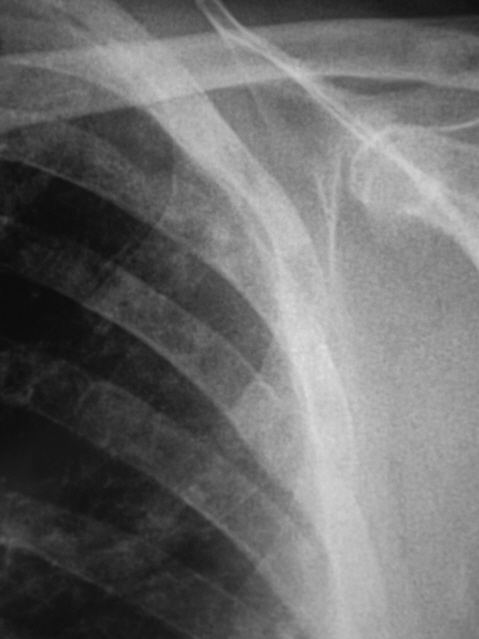

Иллюстрации 1, 2. На обзорной рентгенограмме органов грудной полости, произведенной в прямой стандартной проекции с обеих сторон, на фоне усиленного и обогащенного легочного рисунка определяются множественные полиморфные очаговые тени различных размеров, преимущественно средней интенсивности во всех отделах легочных полей. Тень корней преимущественно левого представляется несколько расширенной, гомогенизированной. Справа в малой междолевой щели плевра утолщена.